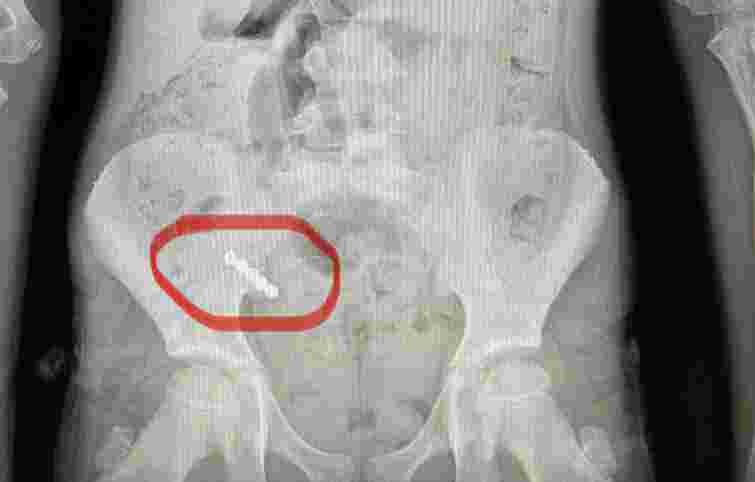

У Волинському обласному медобʼєднанні захисту материнства і дитинства прооперували 9-річну дівчинку, яка проковтнула чотири магніти. Як повідомили 29 квітня на сторінці медзакладу у Facebook, у пацієнтки виник перитоніт (ред. – запалення очеревини), тож сторонні предмети довелося видалити разом із апендиксом.

За інформацією лікарів, 9-річна дівчинка потрапила в медзаклад із підозрою на гострий апендицит. Оскільки клінічна картина була нетиповою, дитині провели додаткові обстеження. Як зʼясувалося, у кишківнику пацієнтки – сторонні предмети.

Під час операції лікарі виявили магніти, два з яких склеїлись між собою у різних відділах кишківника. У місці з’єднання утворився пролежень, а згодом виникла перфорація (ред. – отвір у стінці частини шлунково-кишкового тракту), внаслідок чого кишковий вміст витік у черевну порожнину.

«Магніти було вийняти непросто – їх довелося “завести” в апендикс і видалити разом із ним. Дівчинку виписали додому на 10-й день після оперативного втручання», – розповів дитячий хірург Василь Демчук.